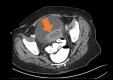

Figure 1

Figure 1. Preoperative CT scan demonstrating thick-walled, mildly enhancing complex fluid collection anterior to the sigmoid colon consistent with a perisigmoid abscess of diverticular origin.

CT: computed tomography